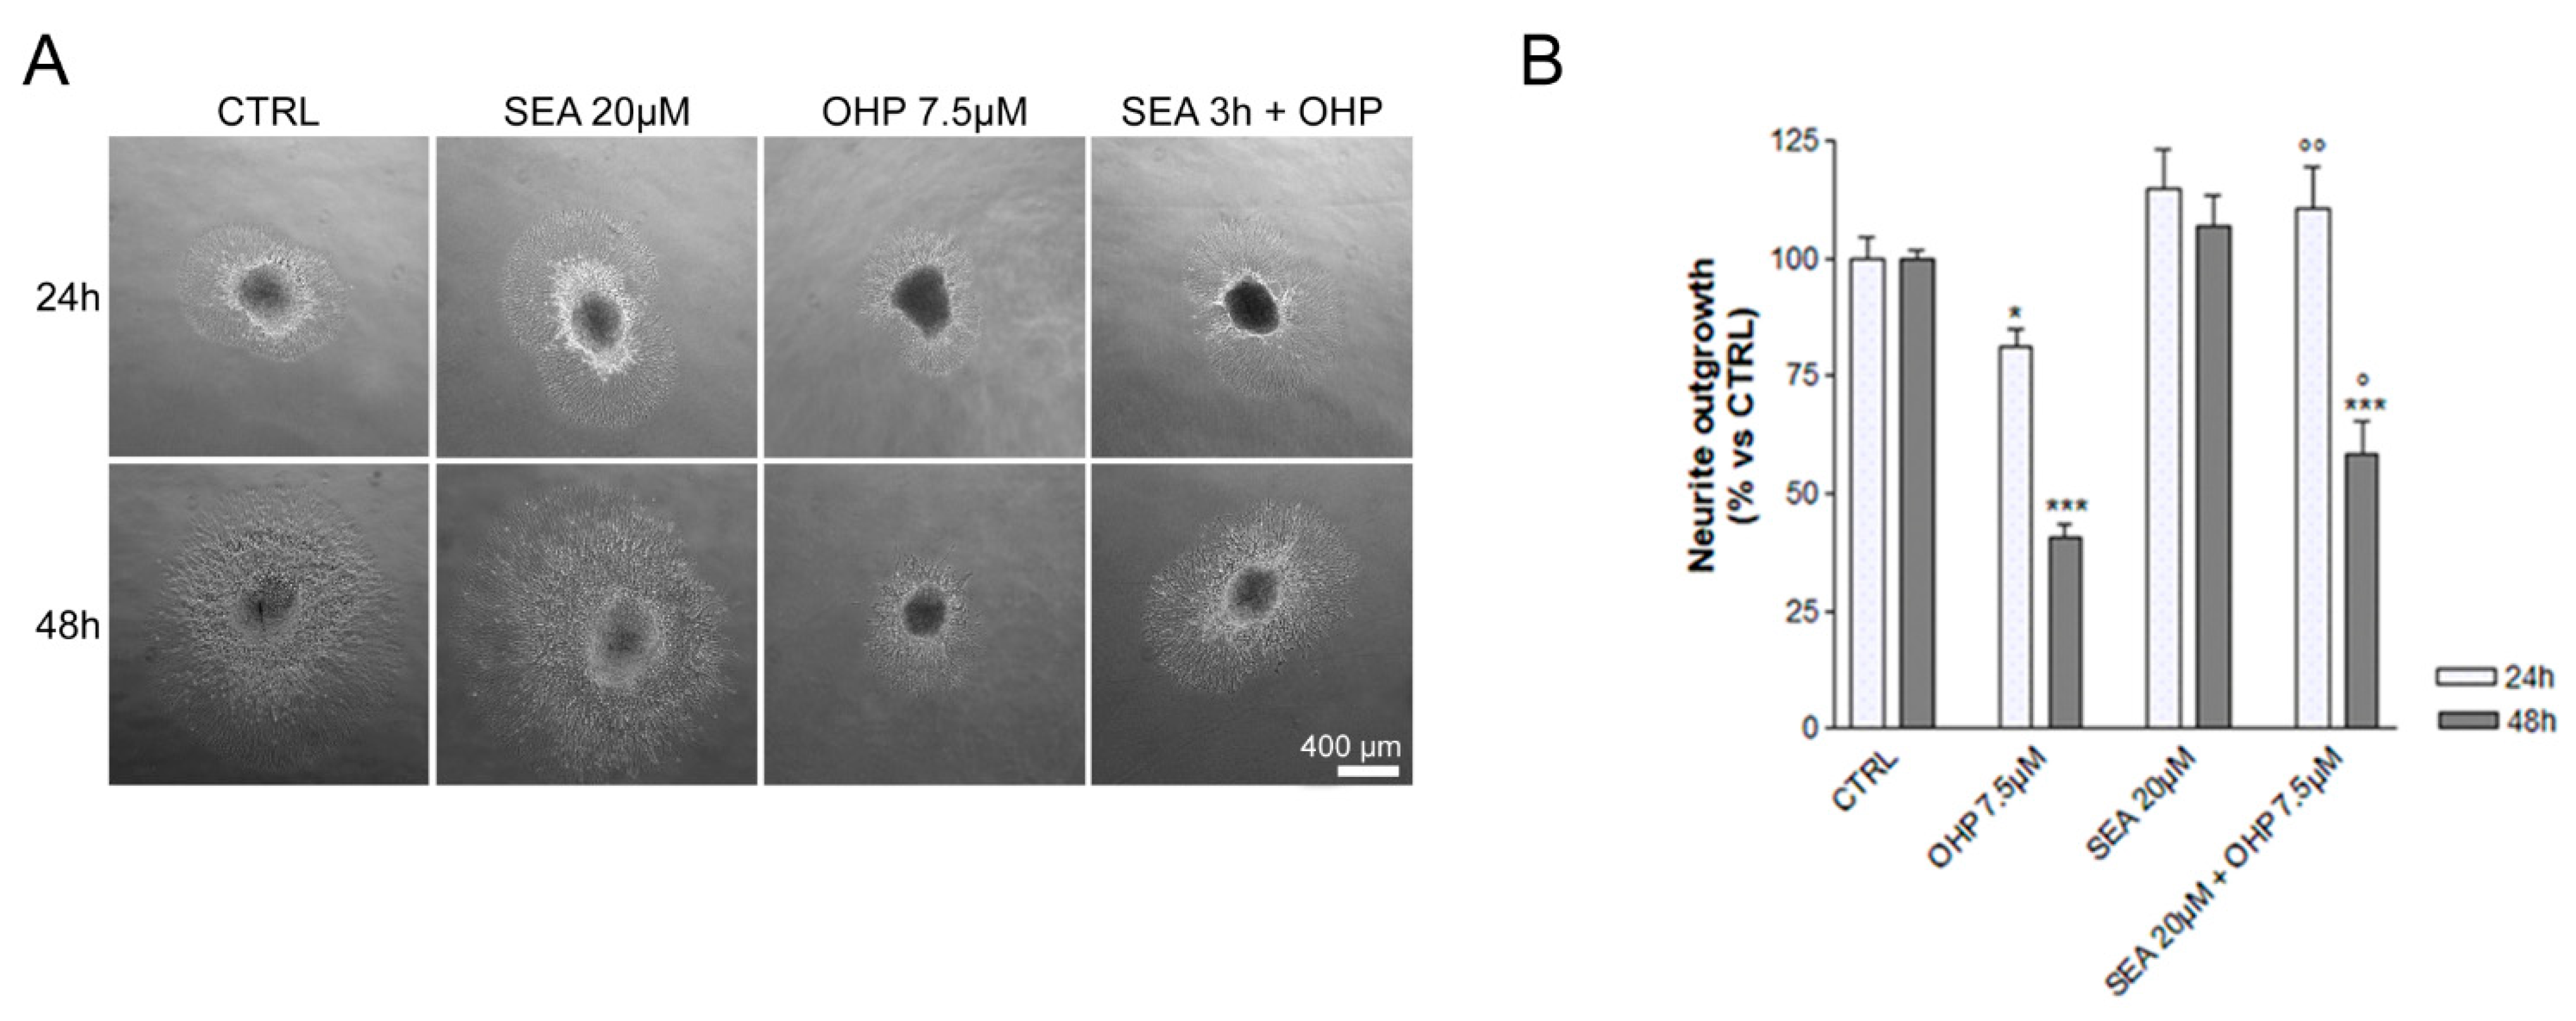

2.1. In Vitro Observations

4.1. In Vitro Experiments

4.1.2. Dorsal Root Ganglia (DRG) Explants